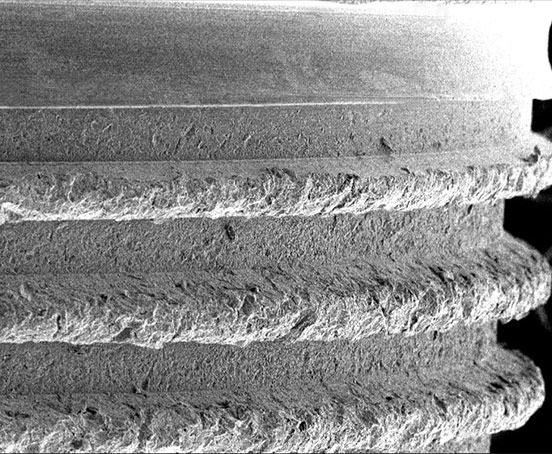

Sharp Buttress Thread

Deep, sharp threads for high primary stability in all bone types

Dual-Led Thread Pattern

Pronounced, dual-lead thread pattern with self-tapping grooves for swift insertion